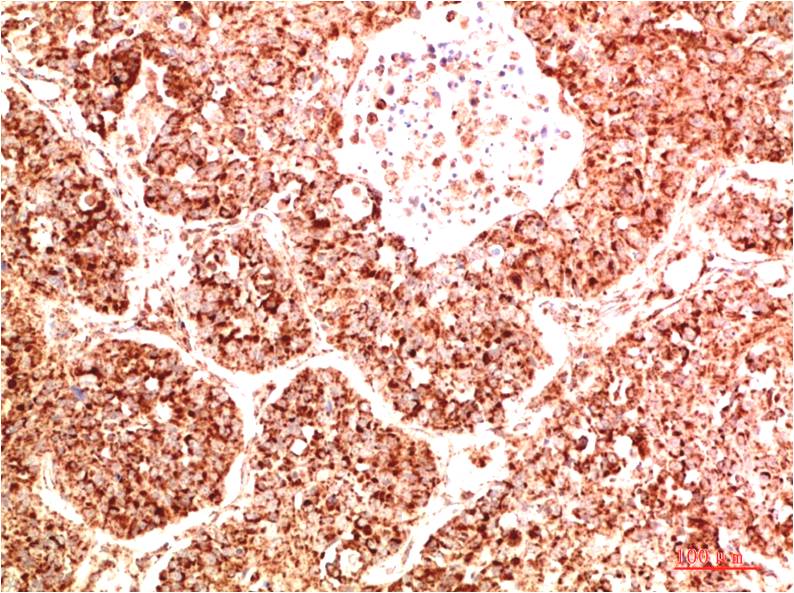

c-Jun Mouse Monoclonal Antibody(4G10)

Applications :IHC

| Recommended dilutions: | IHC 1:100-200 |

| Specificity: | The c-Jun Mouse Monoclonal Antibody can detects endogenous c-Jun proteins. |